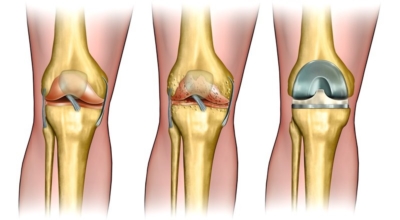

글루코사민에 대조해 원료가 100배가량 비싼 고가의 원료인것으로 알려져 있답니다. 관절염 이유가 되는 것으로는 관절 연골이 닳아 없어지기 때문인데 퇴행성 질환이라고 하는 이유가 연골이 더 이상 생성되기 어렵기 때문이죠. 특히 콘드로이친이라 하는 성분이 나이가 들면서 길이가 짧아지고, 크기가 줄어들기 때문에 연골 구조가 변화되어 가면서 무릎뼈의 간격이 좁아져 통증을 유발하는 원인이 되는데 이 경우에 콘드로이친 효능을 바라볼 수 있답니다.

콘드로이친 효능 중 가장 대표적인 것이 연골세포를 보존하는 역할이라고 합니다. 콘드로이친에는 연골세포의 분해를 억제시켜 연골세포를 보호해주며 유지시켜주는 기능이 있습니다. 연골은 노화가 진행될수록, 나이가 들 수록 점점 그 크기가 떨어지거나 끊어질 수 있지만 이 때에 콘드로이친이 그 스펀지와 같은 역할을 하여 연골 속 수분을 잡아주어 부드럽고 유연하게 유지할 수 있게 도와준다고 알려져 있답니다.

하지만 콘드로이친은 육체 내에서 자연적으로 생성을 할 수 없어 외부에서 추가적으로 보충되어줘야 하는데 나이가 들면서 점점 콘드로이친이 부족하게 되면 무릎이나 손목의 통증, 관절염 등 자연 노화로 인해 피할 수 없이 오는 질환들이 생길 수 있다고 하네요. 그뿐 아니라 아침에 일어났을 때 주로 일어나는 관절 경직 증상 완화에도 큰 도움을 줍니다.

콘드로이친은 대게 골관절염 증상 관리를 위한 치료제로 쓰이고 있답니다. 미국에서 시행된 골관절염 환자 604명을 대상으로 한 연구에서 콘드로이틴의 골관절염 통증 관리의 효과를 관찰했는데 그 결과, 콘드로이틴이 무릎 골관절염 통증이 있는 사람들의 약 10%가 통증완화와 개선효과를 체험했습니다.

그 이유는, 노화가 진행되는 중장년층에게서 콘드로이친 수치가 저하되는걸 볼 수 있습니다. 이는 곧 연골의 뼈와 뼈 사이 완충효과 및 보호기능 약화로 이어지는데 이를 보충하면 관절염을 해결하는데 도움을 줍니다. 그리고 콘드로이친은 관절세포를 재생시키는데 도움이 되고 외부 충격을 흡수, 완화하는데에도 최고의 효과가 있어요.

관절염으로 인한 통증은 환자의 몸의 기능을 쇠약하게 만들기도 합니다. 좀 더 디테일하게 말하자면, 관절염으로 말미암아 몸을 움직이지 않아 일상 활동과 삶의 질에 영향을 미치게 돼요. 한 프랑스에서 모두 만들어진 연구에 근거하면 12개월간 관절염 환자에게 하루에 800mg의 콘드로이친을 제공한 결과 위약을 복용시킨 대조군에 대조해 기능 역량이 50% 안과 밖으로 향상된 결과가 나왔습니다. 또 다른 연구를 보면 콘드로이친 복용이 무릎 관절의 마찰 계수를 감소시키는 것으로 보여 집니다. 즉, 연골이 보다 부드럽게 움직일 수 있도록 도와 관절 기능에 도움되는 것 이예요.